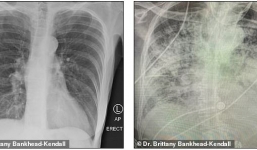

Phim X-quang lá phổi hậu Covid-19 khiến bác sĩ choáng váng